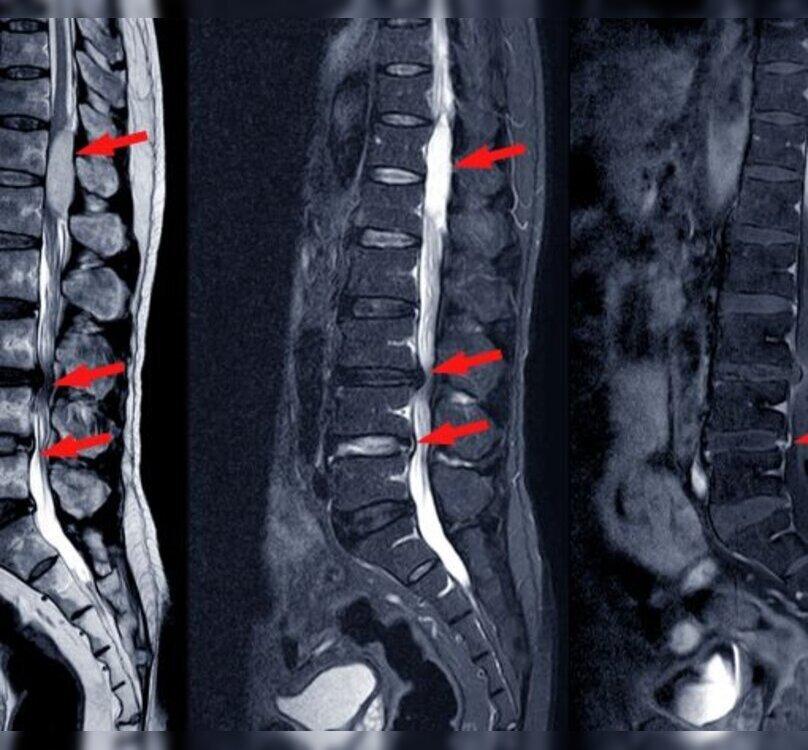

Lumbar spine stenosis is a condition where the spinal canal narrows in the lower back, leading to pressure on the spinal cord and nerves. It can cause symptoms such as back pain, numbness, tingling, and weakness in the legs, which may impact daily activities and overall quality of life.

For more severe cases, surgical interventions like laminectomy or spinal fusion may be recommended. These procedures are performed by experienced spine surgeons in Mumbai's state-of-the-art hospitals, ensuring precise and effective care. Many facilities in the city are equipped with minimally invasive surgical techniques, which offer faster recovery times and reduced post-operative complications.

Advanced stage involving procedures such as laminectomy or spinal fusion to widen the spinal canal and stabilize the spine.